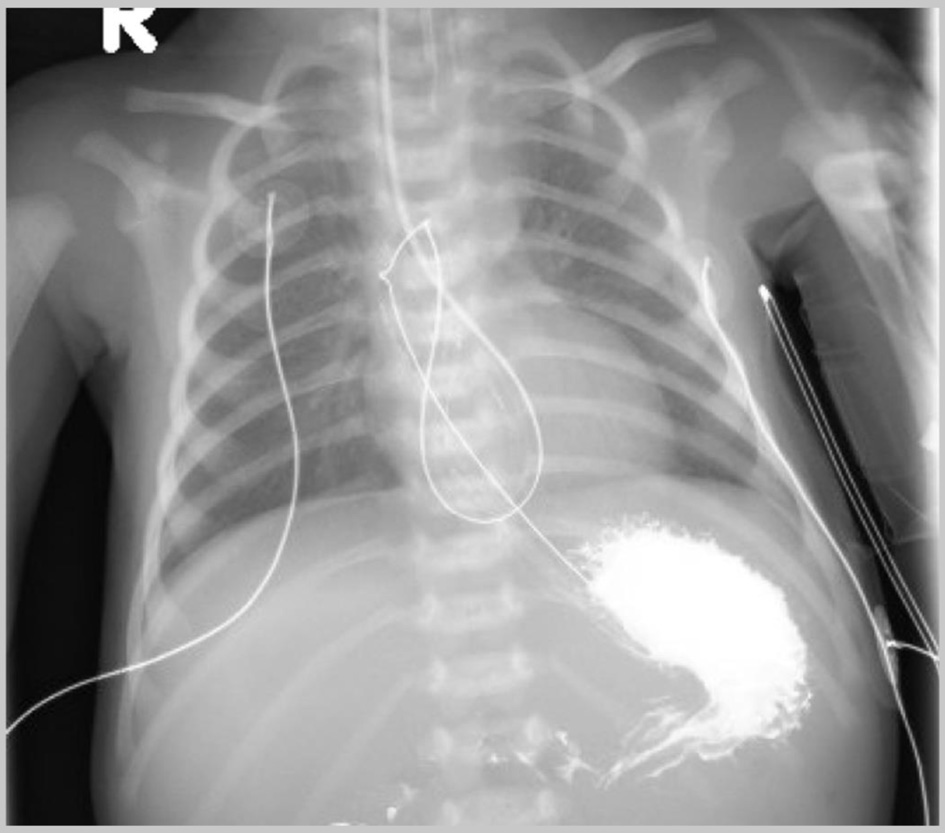

The patient was a 2-day-old, 2.12 kg, premature female infant with history of bilious emesis who presented with duodenal atresia. The patient was taken to the OR for an exploratory laparotomy with plans for a duodenoduodenostomy. Following the induction of general anesthesia and endotracheal intubation, an NG tube was placed for intraoperative decompression of the GI tract. The procedure was tolerated well, and intraoperatively duodenal atresia was confirmed. An intraoperative radiograph was not obtained to confirm NG position. Postoperatively, while the patient was recovering in the NICU, a chest radiograph showed a knot in the NG tube which was positioned in the distal esophagus (Fig. 3). The NG tube could not be removed at the bed side as there was resistance to its withdrawal. Given the newly created duodenoduodenostomy and concern for possible esophageal injury, the patient was returned to the OR, so that the NG tube could be removed under direct visualization and if needed, the esophagus inspected following removal. Following the induction of general anesthesia with an endotracheal tube already in place, direct laryngoscopy was performed by the pediatric otorhinolaryngology service, and the NG tube was removed under direct vision (Fig. 4). The esophagus was not injured. A new NG tube was replaced under direct vision. The patient tolerated the procedure well and upon completion of the procedure was returned to the NICU.

Click for large image

Figure 3. Postoperative chest radiograph obtained after attempted withdrawal of the nasogastric (NG) tube showing the NG with a knot in the proximal esophagus.